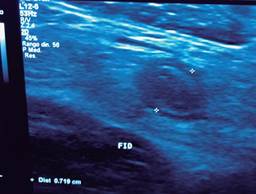

El cirujano general aborda particularmente problemas clínicos que incluyen el aparato digestivo, el cuello, la pared abdominal y los trastornos del sistema circulatorio y el tórax. Un artículo publicado en 2008, por Lindelius,15 demostró que la implementación del ultrasonido por parte del cirujano general en casos de dolor abdominal agudo incrementó en 7.9% la precisión diagnóstica. En la consulta cotidiana de la especialidad, incorporar el rastreo sonográfico al área explorada agrega minutos al examen clínico que aportan datos de notable valor por la objetividad y precisión. El abdomen suele ser el sitio que los cirujanos generales exploramos con más frecuencia. Es posible en una consulta cotidiana hacer todo el protocolo de ultrasonido de abdomen superior en minutos, que incluye ambos cuadrantes superiores y los flancos, pudiendo observar el hígado, la vesícula y los conductos biliares, ambos riñones, el bazo, parte del páncreas y, con ayuda del Doppler color, los principales vasos de la región como la vena cava inferior, la aorta abdominal, la vena porta, los vasos esplénicos y la arteria hepática. Puede haber limitantes como el contenido gástrico, el nivel de llenado de la vesícula biliar o la constitución del paciente y su capacidad de cooperar con el estudio. Pero con la práctica cotidiana, se adquieren las destrezas y el refinamiento suficientes para lograr, con la experiencia acumulada, producir imágenes de relevancia diagnostica inmediata. En la fase de entrenamiento, contrastar nuestros hallazgos con información disponible en la red, con los colegas imagenólogos, o cirujanos ya experimentados en ecografía, permitirá la retroalimentación y la tutoría esenciales de toda curva de aprendizaje. Tradicionalmente se consideraba que aquellos órganos que contienen una mezcla de líquido y gas (intestino, estómago) no son valorables por ultrasonido, el gas produce un efecto rarefacción, ya que no comprime las ondas como un tejido solido o un medio líquido, la señales entonces se dispersan impidiendo que regresen como ecos y permitan al procesador formar una imagen congruente con el órgano explorado. Sin embargo, cuando esta condición cambia como consecuencia de un estado patológico, es posible identificar el contenido intestinal o el gástrico y darnos una idea más aproximada de lo que realmente está ocurriendo en ese abdomen. Podemos, por ejemplo, saber si un estómago está lleno de líquido, o si el intestino contiene residuo sólido, líquido o gaseoso. Los equipos actuales pueden incluso ver en detalle la pared intestinal cuando ésta esté dilatada. Se puede distinguir cuando el colon está ocupado de líquido a nivel del flanco izquierdo como podría ser en una colitis amebiana o en una oclusión intestinal,16 donde se observa dilatación del intestino delgado ≥ 25 mm, el peristaltismo anormal, la presencia de líquido libre intraperitoneal y el edema de la pared intestinal (Figura 2). En casos de dolor abdominal agudo, el ultrasonido puede, en forma inmediata, permitir diagnósticos diferenciales como el hallazgo de una dilatación pielocalicial por nefrolitiasis (Figura 3), o un aneurisma de la aorta abdominal (Figura 4). Un estudio prospectivo realizado en Irvine, California,17 encontró que la a capacidad diagnóstica del médico de primer contacto practicando el ultrasonido para detectar una colelitiasis tiene una especificidad de 87% y una sensibilidad de 82%, mientras que la prueba de ultrasonografía realizada por radiología tuvo sensibilidad de 83% y una especificidad de 86%. Es decir, que, ahorrando tiempo al paciente, el diagnóstico de colelitiasis es factible agregando unos minutos al examen físico inicial. En casos de apendicitis, el método diagnostico considerado como el estándar de oro es la tomografía axial computarizada (TAC). Sin embargo, tiene inconvenientes como su disponibilidad, su costo, el riesgo de radiación en niños y pacientes embarazadas. En tales situaciones, sobre todo en niños, sexo femenino o pacientes delgados, el ultrasonido es una poderosa herramienta que complementa el examen clínico inicial. Las ventajas del ultrasonido frente a la tomografía serian su ubicuidad (ya está en la sala de emergencias), el bajo costo, la ausencia de radiación y el diagnóstico diferencial con causas ginecológicas o genitourinarias de dolor. En apendicitis, la sensibilidad y especificidad de la TAC es de 99.4% y 80.0%, respectivamente. Para el ultrasonido, la sensibilidad diagnóstica es de 83% y la especificidad de 90%. La tasa de apendicectomía negativa es ligeramente mayor en el grupo de TAC que en el del ultrasonido, es decir, 7.1% (3/42) (TAC) en comparación con 4.67% (5/107) (ultrasonido). Hay que recalcar que el ultrasonido es operador dependiente. La experiencia y la calidad del equipo juegan un papel importante.18 La apendicitis tiene varios hallazgos característicos, como la pared edematosa y el aumento de grosor general. Se toman para criterios de positividad una estructura tubular aperistáltica no compresible que mide más de 6 mm de diámetro en el cuadrante inferior derecho (Figura 5).19-21

Figura 3: Dilatación pielocalicial izquierda en un paciente que acude a consulta por dolor abdominal agudo.